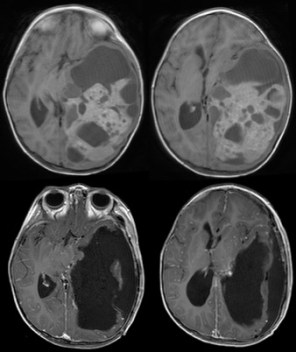

c’est un moyen efficace de prévenir les récidives, et même de faire disparaître un reliquat tumoral postopératoire non extirpable (ci-contre) ; elle est cependant grevée de morbidité en raison de sa neurotoxicité chez les jeunes enfants et du risque de tumeur radio-induite.